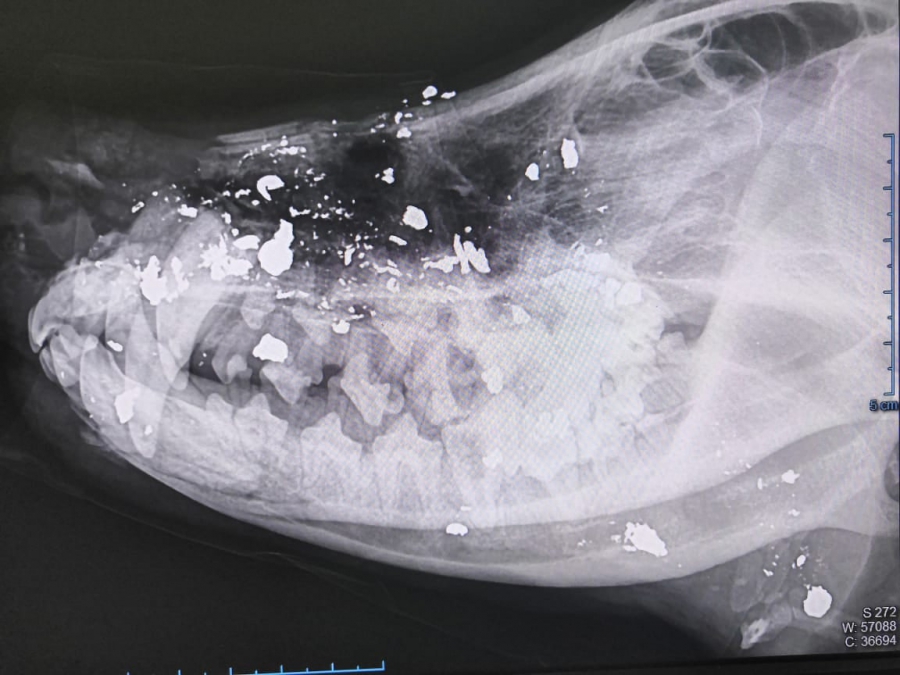

«У него огнестрельное ранение лицевой части, шеи, правой грудной конечности. Оскольчатый, открытый перелом локтевой и лучевой костей справа, с кровотечением!» - рассказали волонтеры.

При обследовании выяснилось, что травмы уже не свежие, они загноились.

За короткое время организация собрала некоторую сумму в качестве помощи. Проведена операция по восстановлению костей, удалили осколки и раздробленные зубы, установлен дренаж. Возможна еще одна операция.